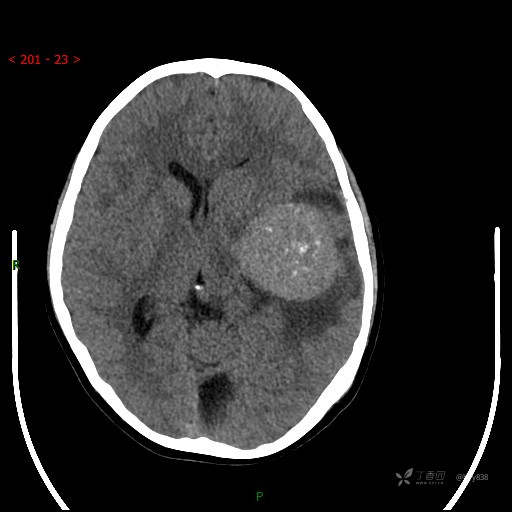

“典藏”病例分享。10岁儿童,头痛头晕一周余,CT、MRI 都有---结果公布~

简要病史:患者于一周前无明显诱因开始出现头痛头晕,无恶心呕吐,无肢体抽搐,无寒颤高热,无腹胀腹泻,无视力下降及视野缺损,上述症状休息后可稍缓解,未引起重视。 2天前患者头痛头晕不适加重,伴有恶心感,无呕吐,遂到当地人民医院行头颅CT检查示:左侧颞部占位性病变,今日家属为求进一步治疗,来我院门诊求治。门诊拟“左侧颞部占位性病变”收入我科。 患病以来,患者精神、饮食、睡眠尚欠佳,大小便如常,体力体重无明显变化。

临床诊断:左侧颞部占位

颅脑CT扫描